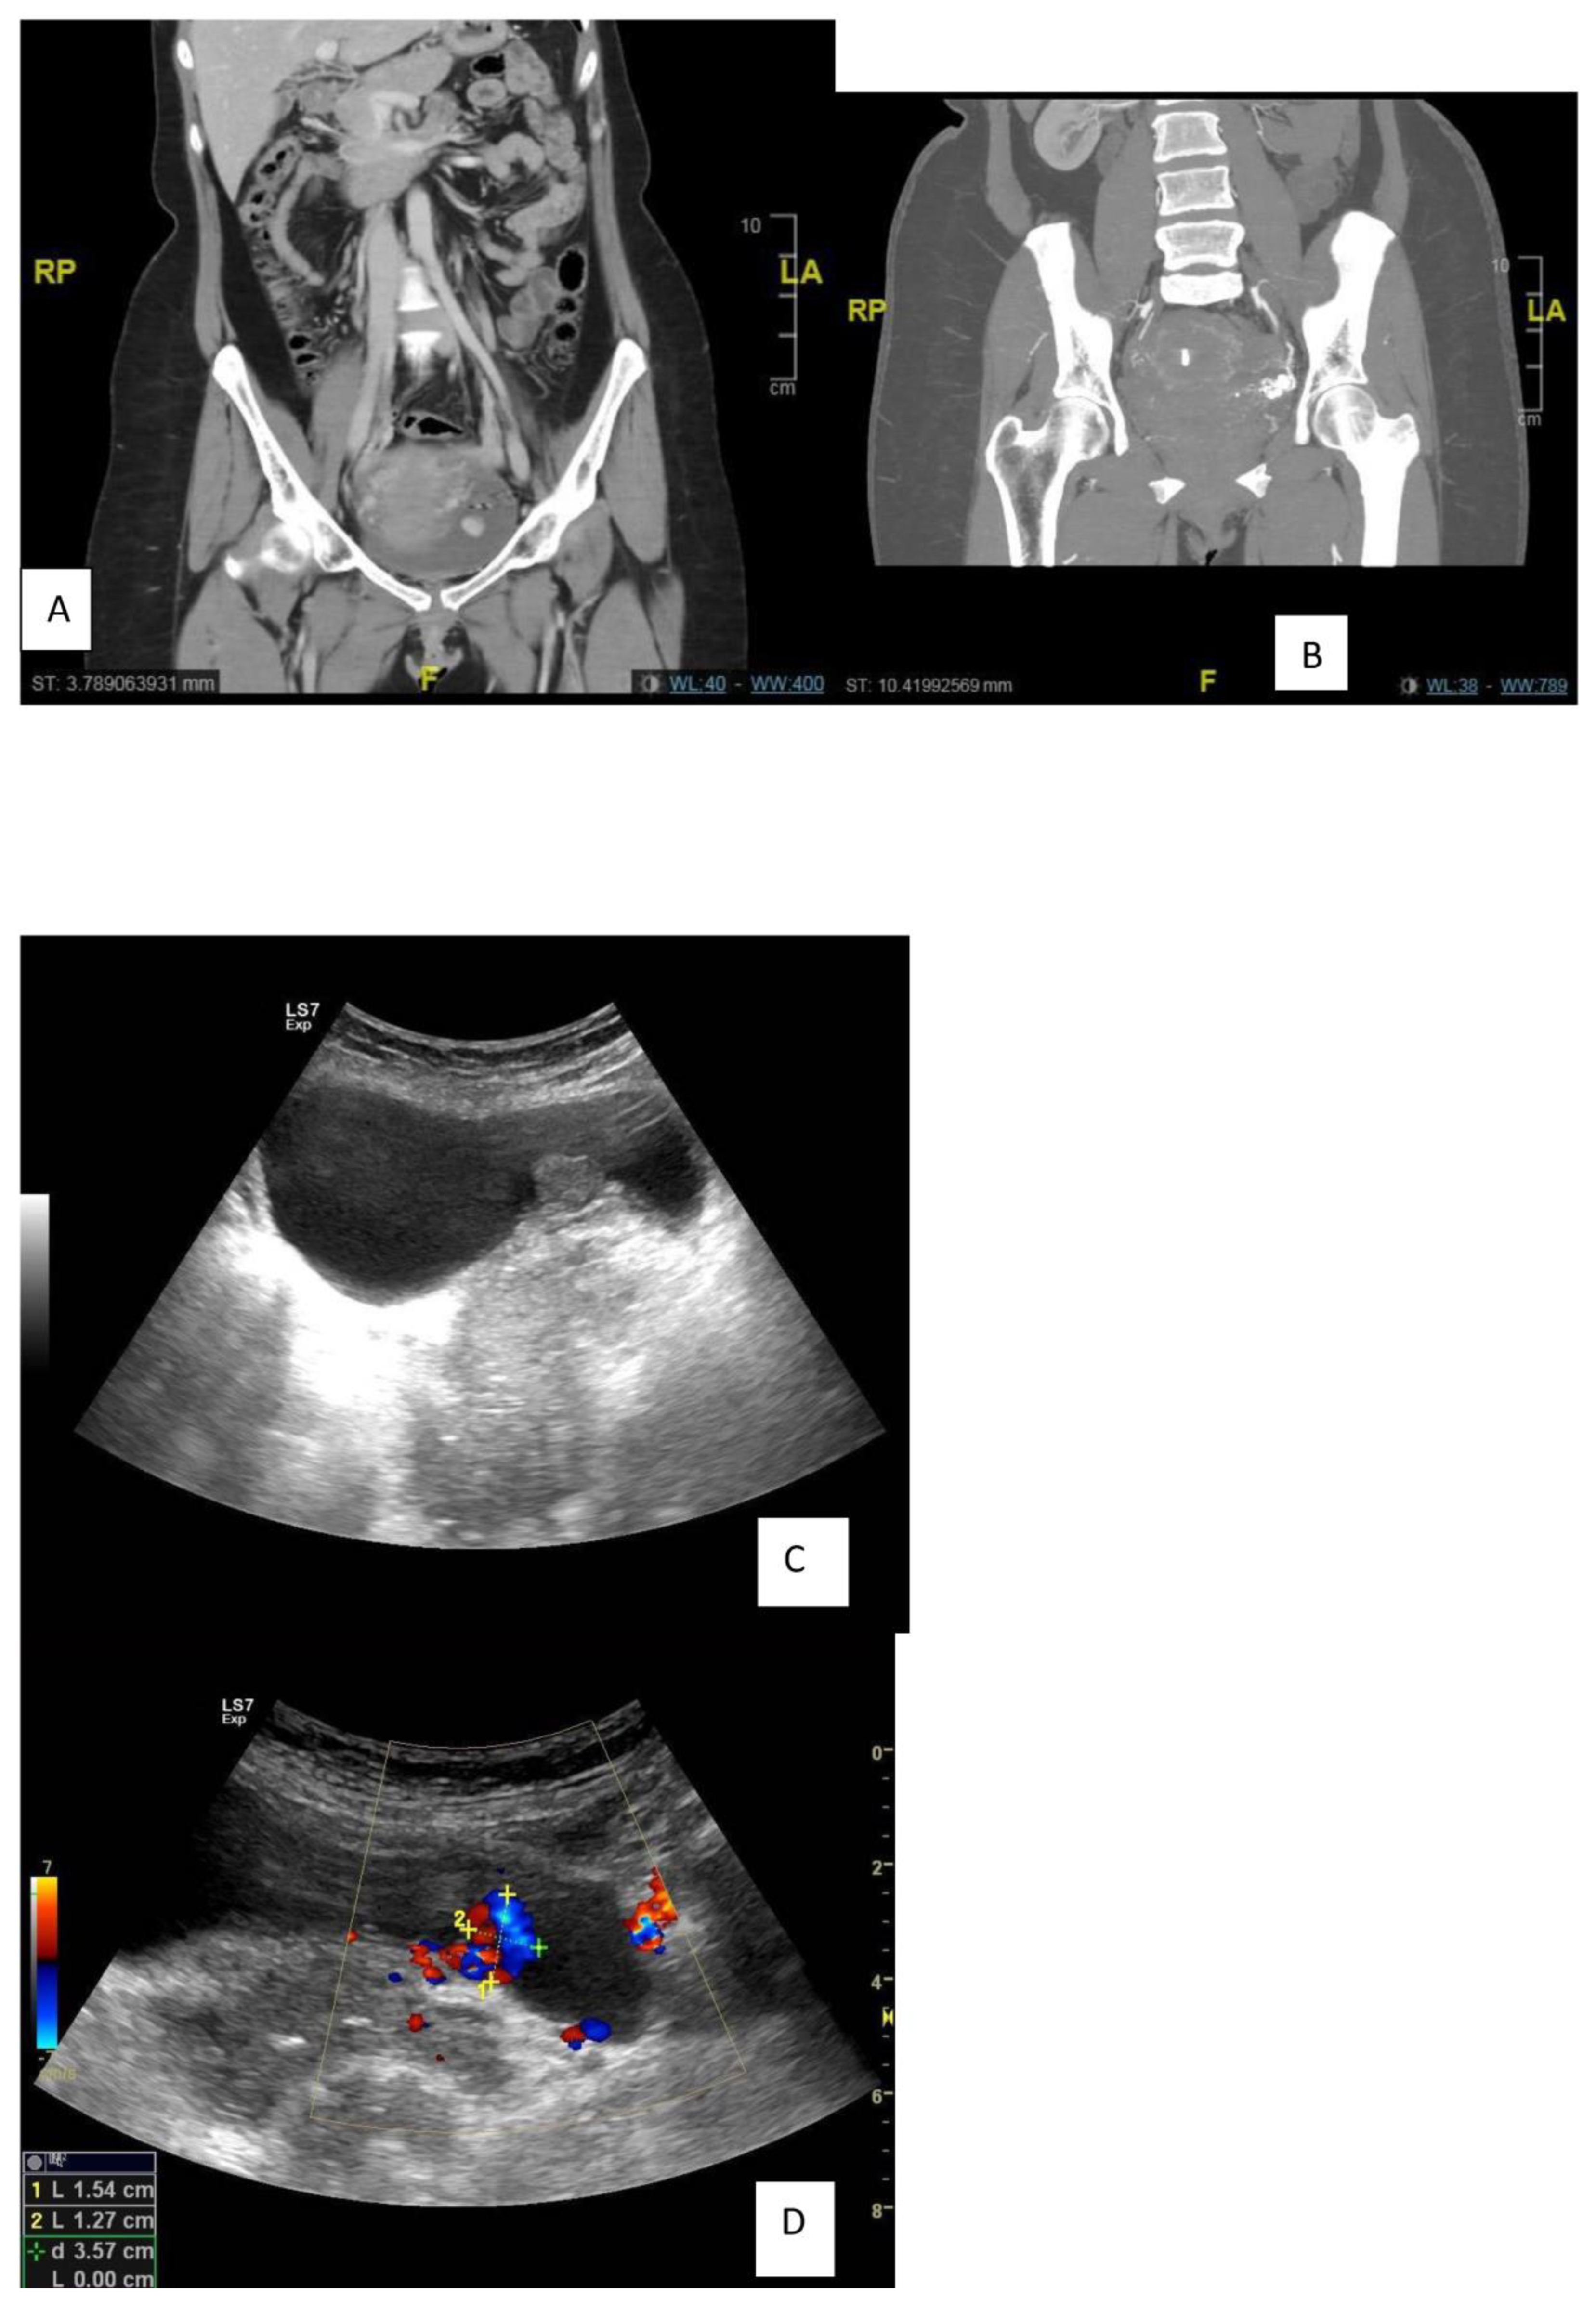

| Ultrasound | Incidental finding of large bladder mass |

| Computed tomography with contrast medium | Showed a 17.1 × 24.2 mm polypoidal hyper-vascular lesion, as previously described, arising from the urinary bladder wall (and thus unlikely to be arising from the anterior wall of the uterus). |

| Cystoscopy | Showed a large, bluish-red, pulsatile, vascularized submucosal mass with large dilated submucosal vessels, a wide-based stalk and no active bleeding in the posterior wall of the urinary bladder, measuring about 2 × 3 cm, with urine cytology negative. |

| In 2018, recurrence after 5 years of follow-up | US showed a distended UB with a polypoidal soft tissue mass measuring 16 × 16 mm with internal vascularity, nidus in afferent and efferent vessels, and turbulence in the flow. |